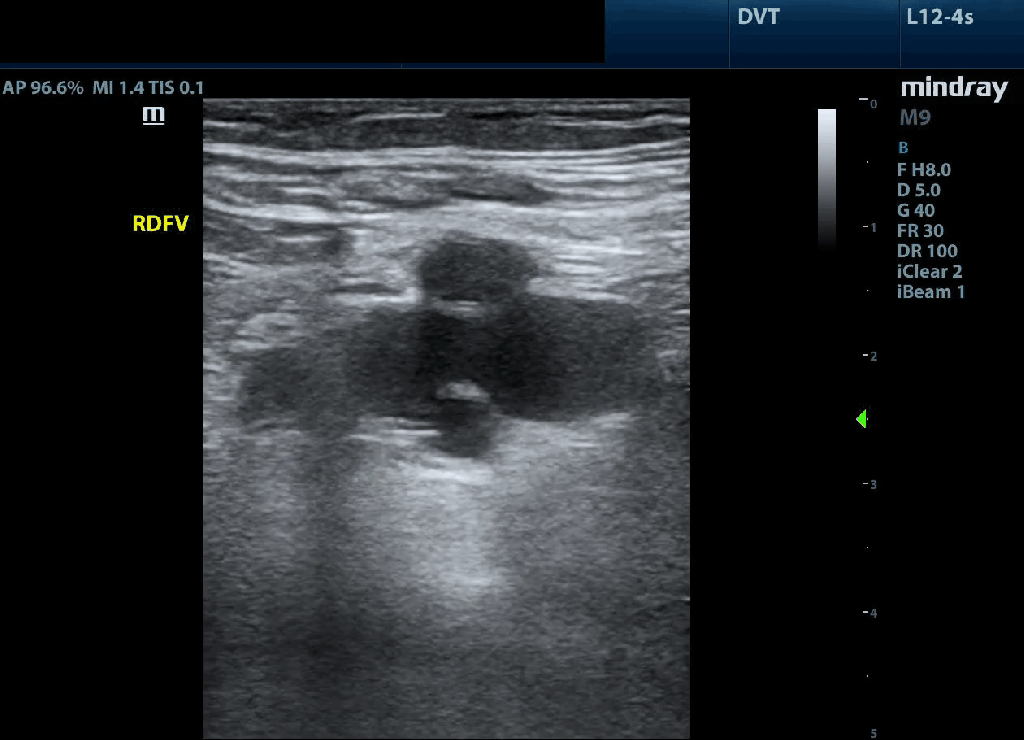

Positive: In this case we are looking at a completely occluded popliteal vein (with no compression applied) and on the immediate right a branch vessel as well. In complete occlusions it might be difficult to discern the vein especially if it is more chronic and more isoechoic with the surrounding tissue. This highlights why it is so important to visualize the artery as it assists with localization.